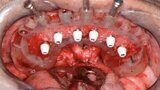

Fig. 3: Pre-op mandibular occlusal view.